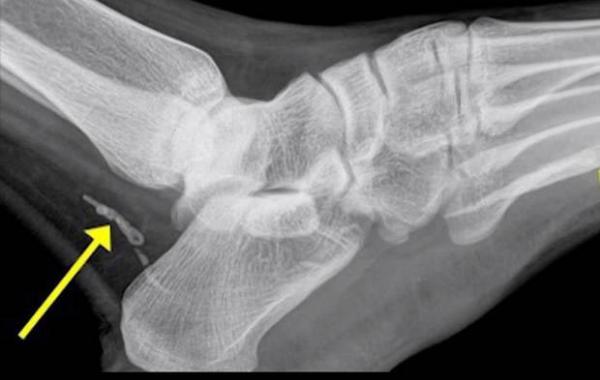

Мужчина думал, что он просто поранил ногу, но правда оказалась гораздо страшнее жесть 16.12.2014 8579